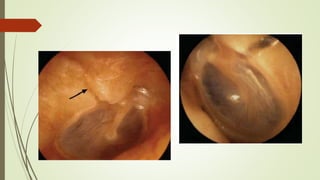

 CAE  Otorrea, hemotimpano, perforación MT, fx de scutum

Hemotimpano Observación resolución espontanea en 6 semanas

Perforación MT  no requiere intervención inmediata

Evaluación Clinica  Signode battle  fractura de base craneal  CAE  Otorrea, hemotimpano, perforación MT, fx de scutum NO IRRIGAR, NO OTOSCOPIA NEUMATICA Hemotimpano Observación resolución espontanea en 6 semanas Perforación MT  no requiere intervención inmediata